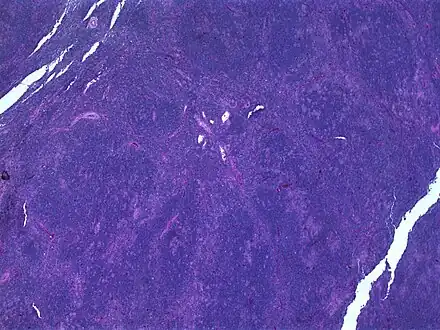

a-e)Clinicopathologic features of cervical nodular lymphocyte-predominant Hodgkin lymphoma Hodgkin lymphoma, nodular lymphocyte predominant (low power view). Notice the nodular architecture and the areas of "mottling". (H&E)

Hodgkin lymphoma, nodular lymphocyte predominant (low power view). Notice the nodular architecture and the areas of "mottling". (H&E) Hodgkin lymphoma, nodular lymphocyte predominant (high power view). Notice the presence of LP cells, also known as "popcorn cells". (H&E)

The characteristics of NLPHL differ from classical Hodgkin lymphoma (cHL).[9] Lymphocyte predominant (LP) ("popcorn") cells are present embedded in nodules consisting of B cells[10] and other reactive cells (mainly reactive T cells).[9] Reed-Sternberg and Hodgkin (RSH) cells are rarely seen, and immunohistochemistry shows a different pattern on the malignant cells; RSH cells typically express CD15 and CD30, whereas LP cells lack expression of these markers, but express B cell markers like CD20, CD22, and CD79a and also express the common leukocyte antigen CD45, which is uncommon on RSH cells.[9] The LP cells have scant cytoplasm and one folded or multilobated nuclei with prominent, mostly basophilic nucleoli.[10] Expert pathology review of multiple morphologic and immunophenotypic features[10] including the use of immunohistochemistry is essential.[11][12]